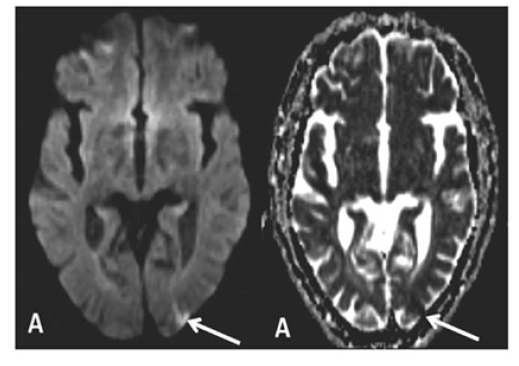

Non-contrast head CT was normal. MRI brain showed two areas of abnormal diffusion restriction in the left posterior parietal lobe and the right cerebellar hemisphere; areas were consistent with acute infarct (Figure 1A). Magnetic resonance angiography (MRA) of the head and neck revealed significant vascular disease including 75-80% left proximal internal carotid artery (ICA) stenosis, left supraclinoid ICA tandem lesions and 65% short segment stenosis of the left vertebral artery. Vertebrobasilar strokes were thought to be possibly related to vertebral artery disease. Transthoracic echocardiogram was normal, revealing only mild left ventricular hypertrophy. Telemetry showed no evidence of arrhythmia. The etiology of stroke was initially attributed to diagnosis of polycythemia, however additional genetic studies were negative, including JAK2 V617F mutation or to vertebrobasilar disease.

Figure 1A:MRI imaging of patient 1, showing evidence of acute infarct in the left posterior parietal lobe on DWI and ADC sequences.